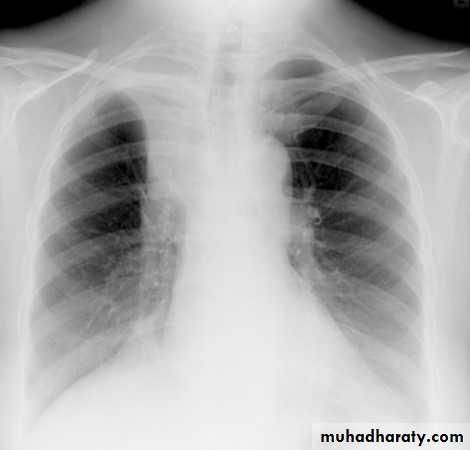

Pancosts tumor

A Pancoast tumour, otherwise known as superior sulcus tumour, refers to a relatively uncommon situation where a primary bronchogenic carcinoma arises in the lung apex and invades the surrounding soft tissues , adeno CA being the most frequent type ,Plain film

Plain films demonstrate a soft tissue opacity at the apex of the lung. Occasionally with rib involvement with extension into the supraclavicular fossa may be evident with surrounded bony destruction . Lordotic views may be helpful .

Pancost tumor